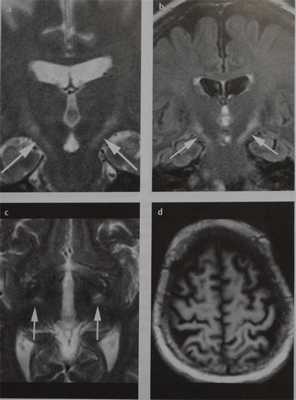

Боковой амиотрофический склероз. МРТ, Т2-ВИ во фронтальной плоскости (а), FLAIR-изображение во фронтальной плоскости (b) и Т2-ВИ в аксиальной плоскости (с). Типичные двусторонние гиперинтенсивные зоны вдоль пирамидного пути (стрелки). Атрофия прецентральной и постцентральной извилин (d).

- На Т2-ВИ, взвешенном по протонной плотности, и РЬАЖ-изображении определяется сигнал высокой интенсивности от пирамидного пути, однако, не только в задней ножке внутренней капсулы, что иногда встречается у здоровых лиц, но и в ножках мозга и лучистом венце (определяется у 78% больных с быстро прогрессирующим течением и у 12% больных с медленно прогрессирующим заболеванием)

- Низкий сигнал от коры прецентральной извилины на Т2-ВИ (повышенное депонирование железа)

- Иногда интенсивность сигнала повышена и в шейном отделе спинного мозга.